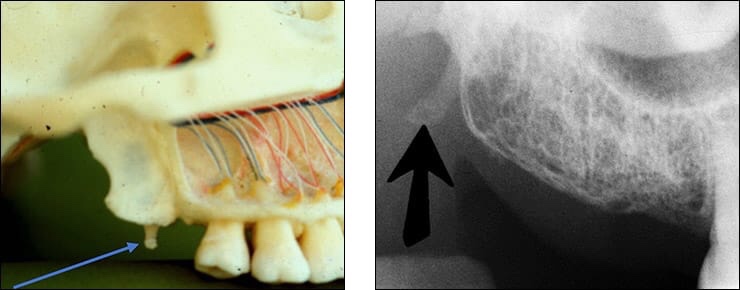

6) Mandibular Posterior Landmarks

• Mental foramen – Appear as round slit like irregularity, partial or completely cortical radiolucency located in apical region of premolars.

• External oblique ridge – The external oblique ridge or line is the bony anterior border of the ramus located on the outer aspect of the mandible. This ridge has a downward diagonal course. Radiopaque.

• Internal oblique ridge – Irregular crest of bone on lingual surface of body of mandible. It runs parallel to but below the external oblique ridge. The internal oblique ridge is sometimes referred to as the mylohyoid line.

• Mandibular canal – Tube like passage through bone that travels along the length of mandible in contact with the apex of third molar.It is also referred to as the inferior alveolar nerve canal.

• Submandibular fossa – It is scooped but depressed area on bone located lingually below the myelohyoid ridge.This structure is also referred to as the submandibular gland fossa or mandibular fossa.

• Inferior border of mandible is the lower most part of the mandible. Appears as dense broad radiopaque band of bone.

• Coronoid process – It appears as triangular radiopacity with its apex divided & in the region of the third molar. Narrow in lateral dimension. The coronoid process is the only mandibular structure recorded on maxillary molar periapicals.